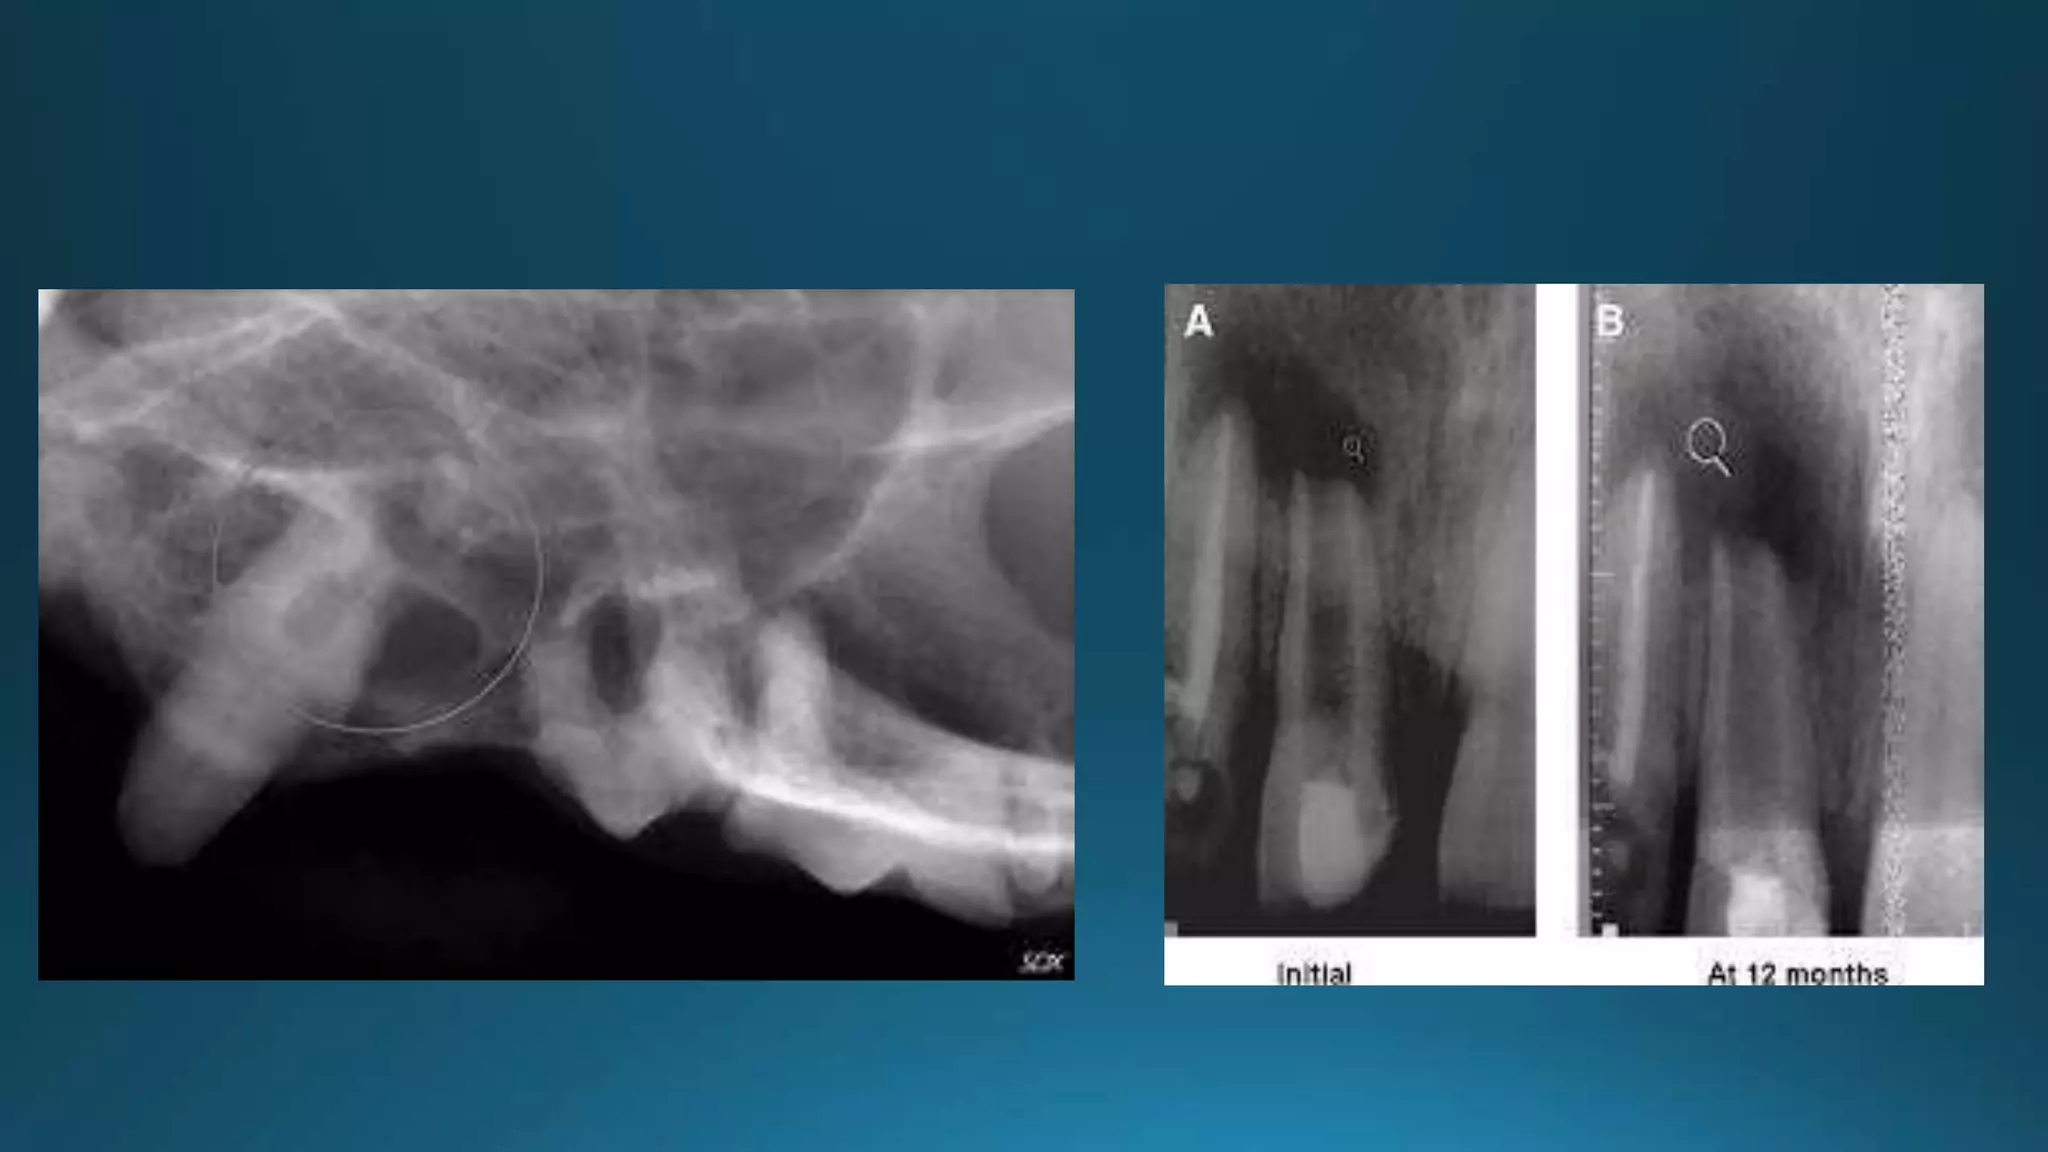

THIN “PINCHED” APEX

BULBOUS APEX

RESORBED APEX

BLUNDERBUSS APEX

Treatment of open apex with no vital pulp

Treatment of open apex with vital pulp

Pulpotomy is indicated to allow

completion of apical closure as long as

pulp remains vital – apexogenesis